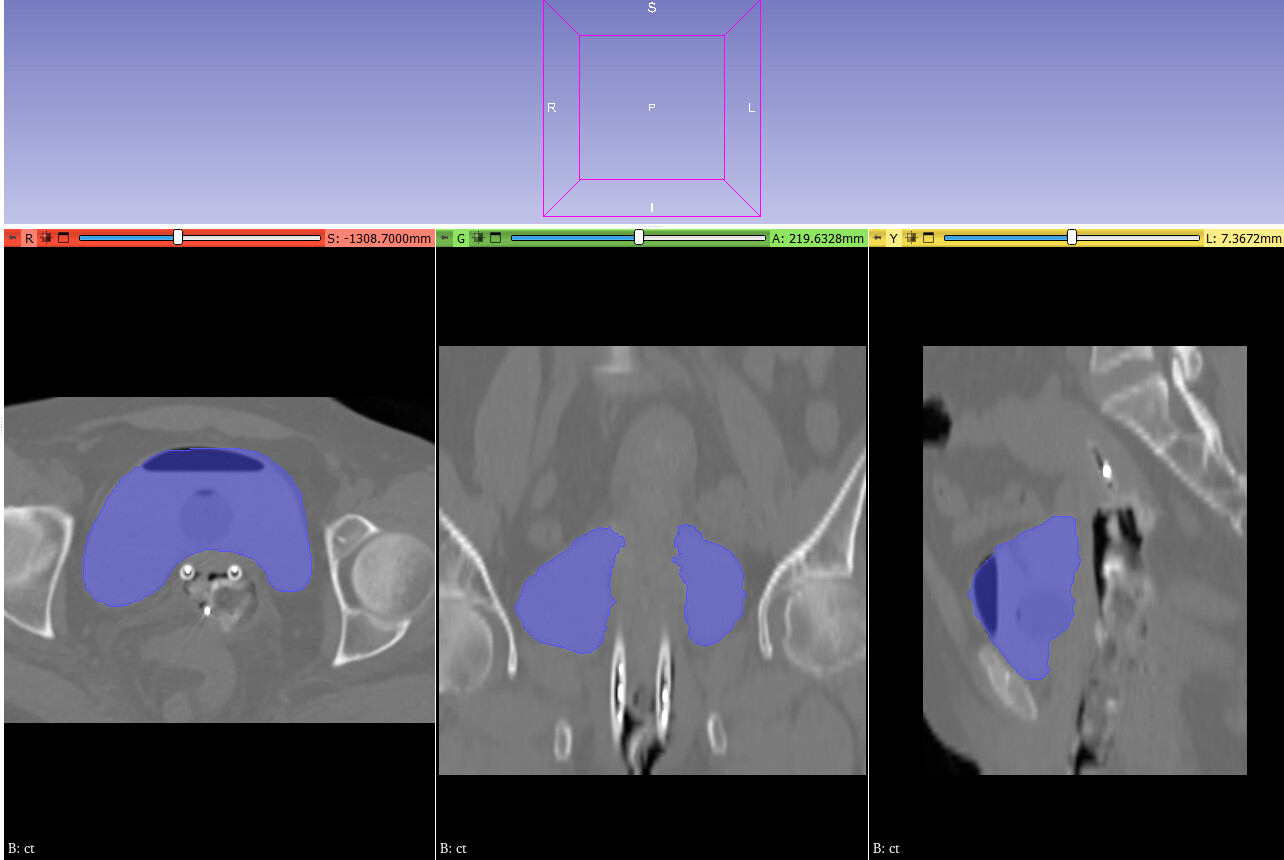

I am working on displaying CT images in the axial, coronal, and sagittal planes, along with dose maps and RTSTRUCT contours. While the CT and dose images are displayed correctly, I am having trouble overlaying the structures (contours) from the RTSTRUCT file on the CT images—the contours do not align properly with the CT, as shown in the attached image.